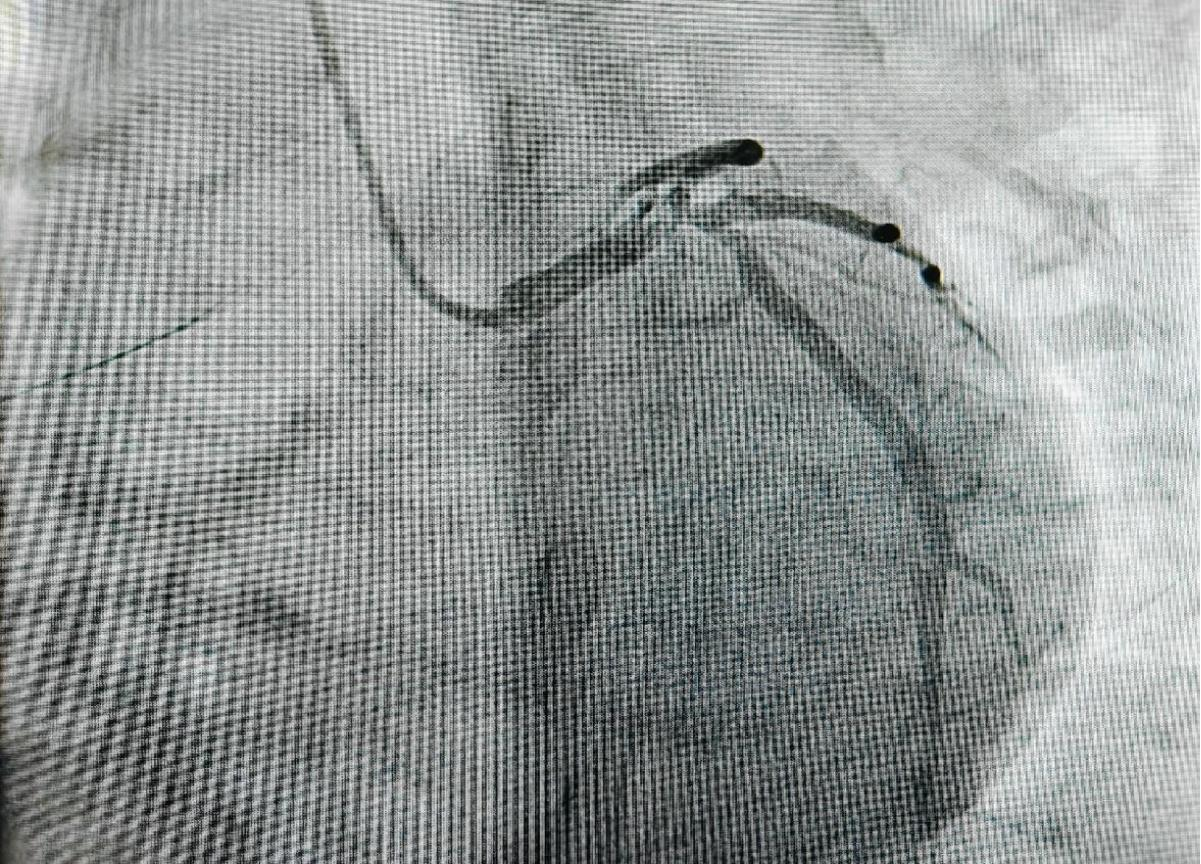

患者最初因胸痛前往当地财神捕鱼 就诊,当地财神捕鱼 通过冠脉造影检查发现,患者左主干末端呈现真性四分叉病变,且多支血管存在严重狭窄的情况,病情十分危急。鉴于患者病情的复杂性,当地财神捕鱼 联系了财神捕鱼 ,随后患者转入院内进一步治疗。心血管内科楚天舒团队接诊后,立即启动应急响应机制,从决定为患者实施ECMO上机,到成功建立循环支持,仅耗时28分钟,为抢救患者赢得了宝贵时间。本次手术中,手术团队创造性运用主动脉内球囊反搏(IABP)+体外膜肺氧合(ECMO)双循环支持系统(IABP + ECMO), ECMO能够有效确保患者的血液循环稳定, IABP可以减轻心脏负担,改善心肌供血,两者协同配合,大大降低术中心脏骤停的风险,极大地提高了手术的安全性。

手术实施双主刀制度,由心血管内科介入团队与MICU紧密合作,确保循环支持与血运重建同步进行,全方位保障手术的顺利开展。术后,采用目标导向镇静策略,精准管理确保患者在48小时内成功撤除ECMO,有效降低了患者术后并发症。